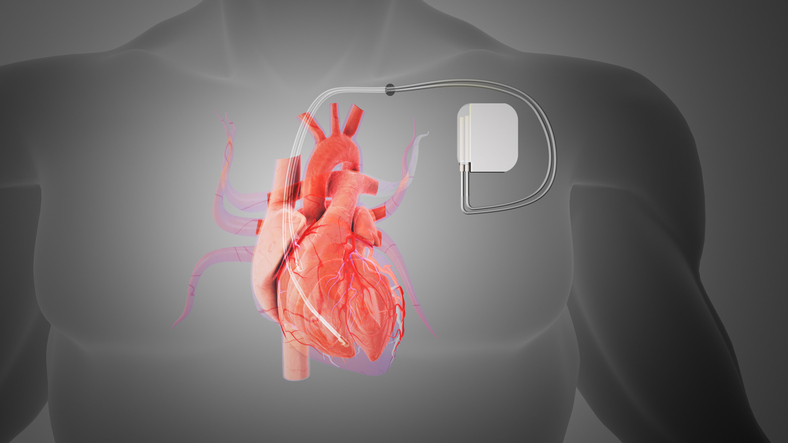

A study found an overall decline in surgical myectomy with ICD procedures since 2016.

Individuals with cardiac implantable electronic devices have a higher risk of tricuspid regurgitation.

BC survivors undergoing CIED placement have a higher risk of periprocedural complications.

There have been dramatic improvements in remote monitoring among both urban and rural patients with CIED.

For patients with CIEDs who undergo remote monitoring, routine in-person visits may not be needed.

Researchers assessed the safety of rides for patients with cardiac implantable electronic devices.

Frailty significantly increases the risk of both in-hospital mortality, and complications in HFrEF patients following CIED.

Over half of of adolescents with cardiac implantable electronic devices have abnormal health screens.